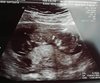

Super wiadomosci! Gratulacje [emoji173][emoji173][emoji173] duzo zdrowka dla Was [emoji173][emoji173]Ja już po badaniu prenatalnym. Na USG wszystko wyszło ok, serduszko, żołądek, kość nosowa i karkówka, także nie ma powodu do zmartwień. Maleństwo ma już 5,7 cm [emoji7]Zobacz załącznik 874392